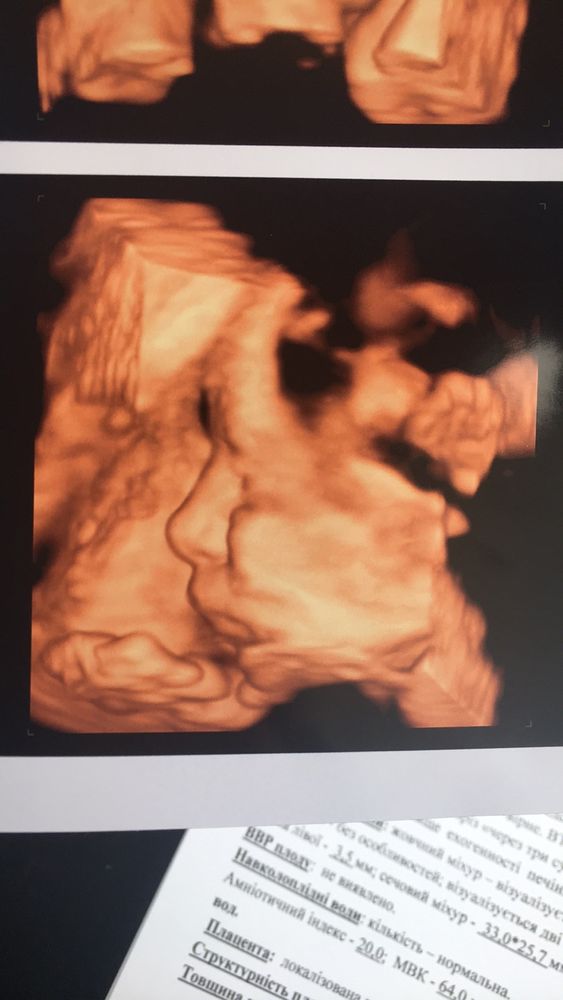

и наконец-то нам сделали фото😍

на прошлом узи он рукой закрылся)) сегодня тоже, но потом смиловался и показал свое личико)

носик мой🥰